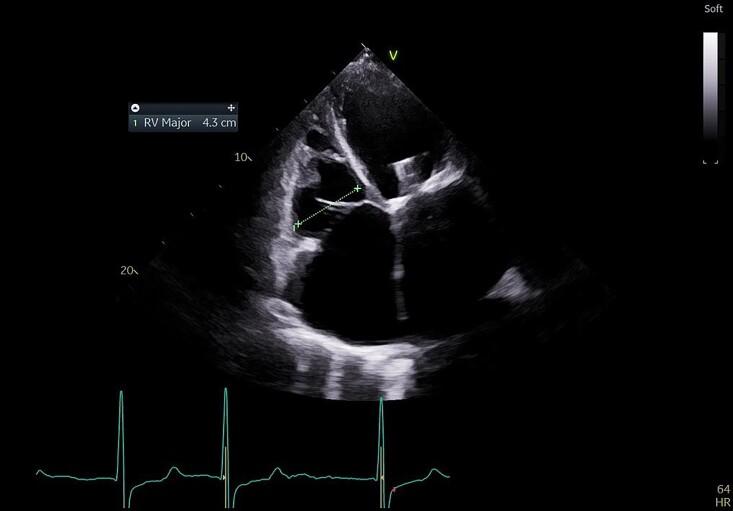

A 69-year-old woman presented with recurrent hospital admissions for right heart failure refractory to medical therapy, on the background of a single-chamber permanent pacemaker (Biotronik) implanted 6 years ago for tachycardia-bradycardia syndrome. Transoesophageal echocardiography identified severe TR which was predominantly CIED-induced from a lead impingement of the posterior tricuspid valve (TV) leaflet preventing adequate leaflet coaptation. This had progressed to cause a degree of secondary functional TR. The patient underwent pacing lead extraction followed by epicardial lead placement via minithoracotomy, with significant symptomatic and echographic improvement of TR.

一名69岁女性因右心衰竭反复住院,药物治疗无效,6年前因心动过速-心动过缓综合征植入单腔永久起搏器(百多力)。经食管超声心动图检查发现严重TR,主要由CIED引起,因导线压迫三尖瓣(TV)后叶,导致瓣叶无法充分对合。这已发展为一定程度的继发性功能性TR。患者接受了起搏导线拔除,随后通过小切口开胸进行心外膜导线植入,TR的症状和超声心动图表现有显著改善。